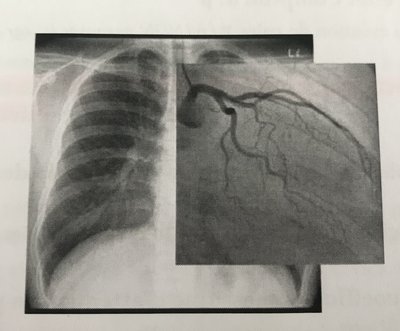

L'iode à un Z très élevé et un coefficient linéique d'atténuation encore plus important que les Os du coup les RX seront beaucoup plus atténués mais le problème c'est que les coronaires avec le contraste iodé apparaissent en noir alors que si j'ai bien compris plus c'est atténué par effets photoélectrique plus c'est blanc du coup je ne comprend pas trop.

Donc déjà tu sais que ton produit de contraste pour être efficace il faut qu'il soit très riche en électrons donc avec un Z important. Ainsi, il va atténuer de façon importante les RX par effet photo-électrique. Tu sais que grâce à un écran luminescent on va pouvoir changer la longueur d'onde des RX afin de les rendre visibles. Moi je me disais: ceux qui arrivent à traverser le patient, ils vont faire de la "lumière" du moins on va les voir donc ce sont les zones en blanc alors que les zones riches en électrons comme les os etc... on ne verra pas les RX car ils on été atténués (ils ne traversent pas les os) donc la zone apparaîtra noire. C'est comme dans un verre si tu mets de l'eau tu vois de l'autre coté: la lumière traverse l'eau sans être atténuée alors que si tu mets du coca elle sera plus atténuée donc elle traversera moins et donc on la verra moins de l'autre côté du verre. :wink2: Du coup quand tu mets l'iode dans le cas d'une coronarographie bah tu verras les coronaires en noir car l'iode a atténué les RX à cet endroit là étant donné qu'on l'a injecté dans les coronaires?

Ah d'accord j'avais pas compris, je pense que ça dépend peut-être de la résolution ou des réglages mais l'essentiel c'est que ça crée du contraste. Regarde sur la ronéo la photo de l'abdomen et du pelvis, tu vois bien qu'avec l'iode même si ça apparaît en blanc les voies urinaires son visibles alors que sans on ne les voient pas.